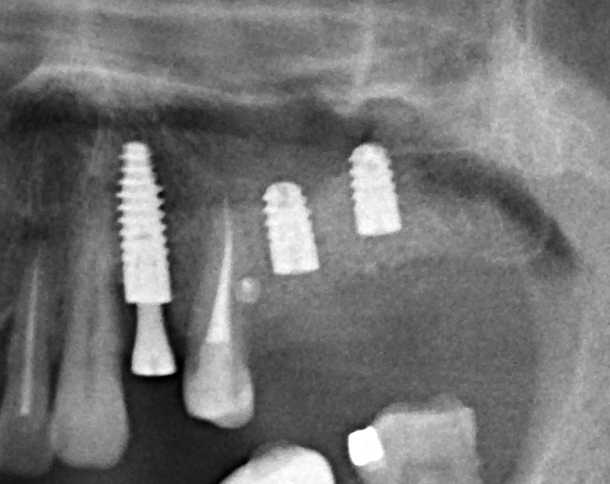

Имплантация и остеопластика: вместе или врозь? Часть II плюс Ankylos, плюс Geistlich